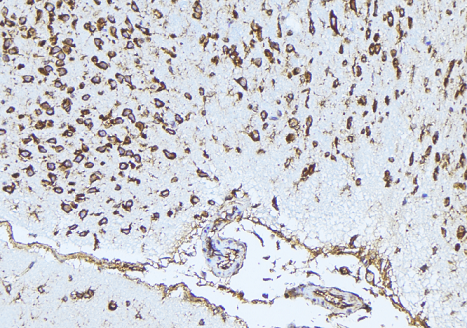

IHC (Immunohiostchemistry)

(AAA323318 at 1/100 staining Mouse brain tissue by IHC-P. The sample was formaldehyde fixed and a heat mediated antigen retrieval step in citrate buffer was performed. The sample was then blocked and incubated with the antibody for 1.5 hours at 22 degree C. An HRP conjugated goat anti-rabbit antibody was used as the secondary.)